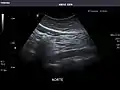

Aorta: Visualized portions normal in caliber, 16 x 15 mm.

Standard measurement of the abdominal aorta[4]

It can be used on the abdominal aorta to detect or exclude abdominal aortic aneurysm. For this purpose, the standard aortic measurement for abdominal aortic aneurysm is between the outer margins of the aortic wall.[4]